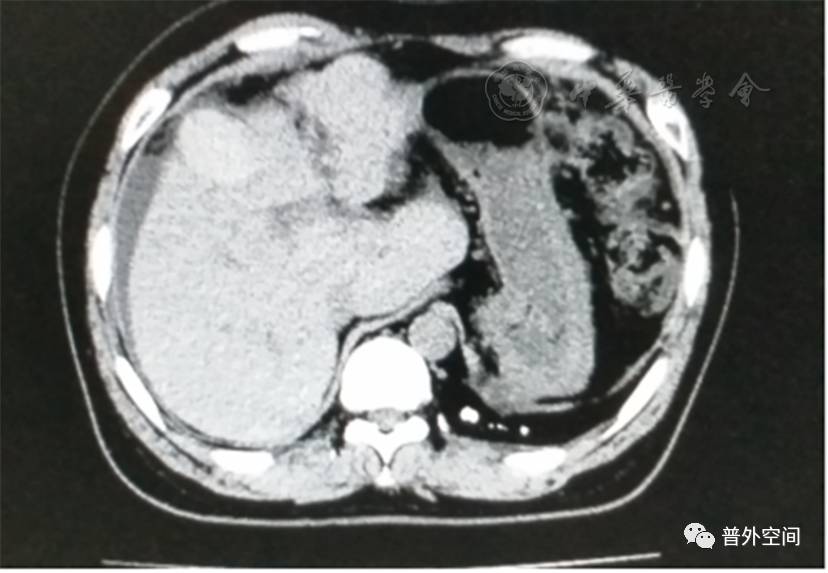

我们将这种方法应用到100多例没有艾滋病病毒感染的一般肝硬化患者身上,结果收到更好的疗效。例如1例男性患者,56岁,失代偿期肝硬化大量腹水合并脐疝(见封四,图1)。CT检查提示肝脏明显萎缩,肝脏体积1 302 ml,大量腹水,脾脏肿大(见封四,图2)。在多家医院就诊后都认为需要做肝移植。我们对患者进行脾切除加脐疝修补,自体骨髓经门静脉输注治疗。手术后3个月,肝功能Child-Pugh分级从C级转成*级A**,手术后1年,肝功能正常,腹部伤口愈合良好(见封四,图3)。CT检查提示肝脏明显增大,体积1 796 ml,腹水基本消失(见封四,图4)。对于肝功能C级的患者手术风险比较高,围手术期输注白蛋白、凝血酶原复合物、纤维蛋白原,改善肝脏功能,手术中经胃网膜右静脉插管埋置骨髓输注设备,输注自体骨髓。随着自体骨髓干细胞在肝内发生复杂的变化,肝硬化组织中的胶原纤维被降解和吸收,肝脏组织的增生和体积增大,肝功能好转,门静脉压力会逐渐降低。但是在手术后1年内,仍然有可能随时发生上消化道出血,需要经胃镜检查,套扎食管黏膜下明显曲张的静脉血管。这样我们做脾脏切除解除脾功能亢进,不做贲门周围血管离断,减少了手术损伤。食管黏膜下静脉曲张用胃镜下套扎治疗。待肝硬化逐渐逆转,食管黏膜下静脉曲张程度将会逐渐减轻。

图4 1年后对比手术前同一部位CT断层照片